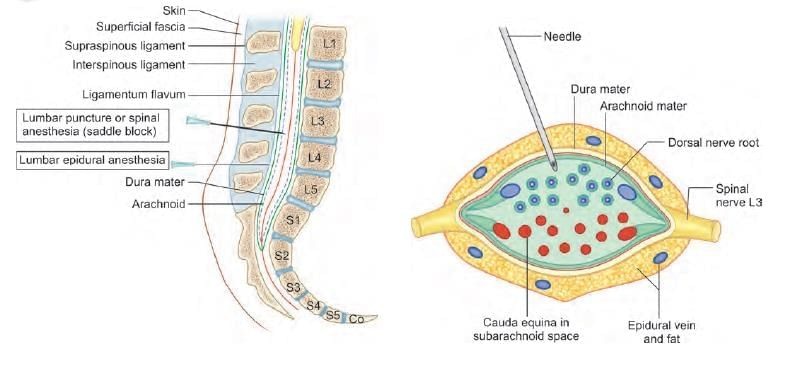

While doing lumbar puncture, which of the following structure is pierced before entering the lumbar cistern? (NEET-PG 2021)